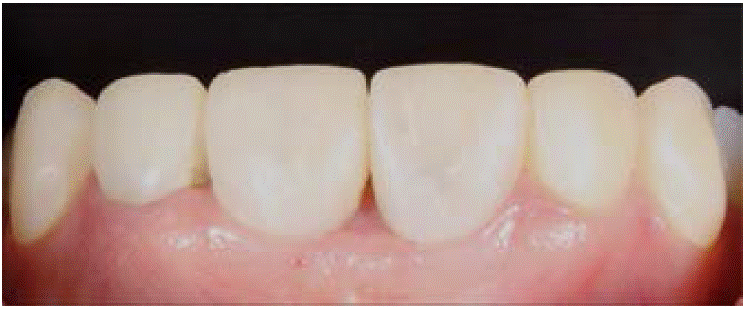

A la exploración clínica observamos una falta de tejido periimplantario, específicamente en las papilas entre los dientes 1.1, 2.1 y 2.2. Presencia de gingivitis localizada debido a la mala integración de provisiona les en los mismos dientes (Figura 1).